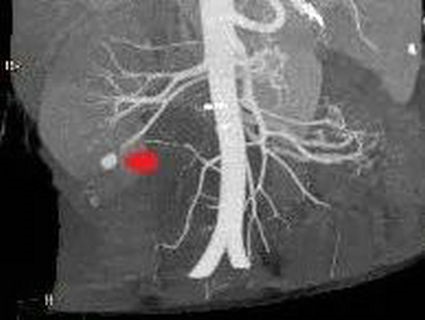

▲ 左图红色箭头为肾动脉分支动脉瘤,右图红色箭头为栓塞治疗后效果

时间就是生命,在吕军主任医师的指导下,通过术中肾动脉造影,发现肾动脉分支动脉瘤,找出了问题所在,微导管到位、颗粒栓塞一气呵成,病人血尿颜色变淡,手术治疗取得圆满成功。根据术后随访,杨大哥未再出现血尿,并已于近日出院。